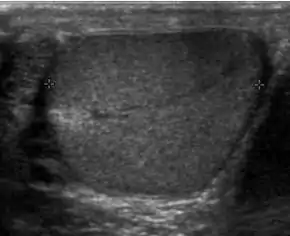

![]() Sonography of a normal testis. The normal testis presents as a structure having homogeneous, medium level, granular echotexture. The mediastinum testis appears as the

hyperechoic region located at the periphery of the testis as seen in this figure. | |

The normal adult testis is an ovoid structure measuring 3 cm in anterior-posterior dimension, 2–4 cm in width, and 3–5 cm in length. The weight of each testis normally ranges from 12.5 to 19 g. Both the sizes and weights of the testes normally decrease with age. At ultrasound, the normal testis has a homogeneous, medium-level, granular echotexture. The testicle is surrounded by a dense white fibrous capsule, the tunica albuginea, which is often not visualized in the absence of intrascrotal fluid. However, the tunica is often seen as an echogenic structure where it invaginates into the testis to form the mediastinum testis. In the testis, the seminiferous tubules converge to form the rete testes, which is located in the mediastinum testis. The rete testis connects to the epididymal head via the efferent ductules. The epididymis is located posterolateral to the testis and measures 6–7 cm in length. At sonography, the epididymis is normally iso- or slightly hyperechoic to the normal testis and its echo texture may be coarser. The head is the largest and most easily identified portion of the epididymis. It is located superior-lateral to the upper pole of the testicle and is often seen on paramedian views of the testis. The normal epididymal body and tail are smaller and more variable in position.